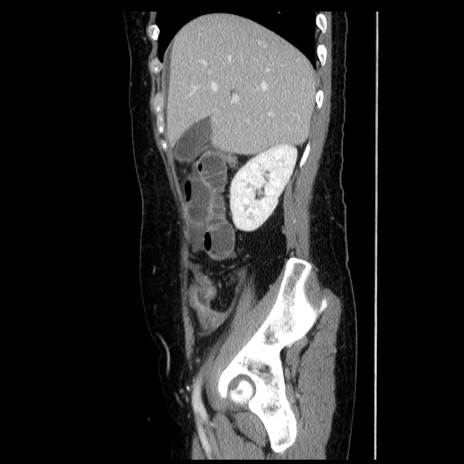

冠状断像